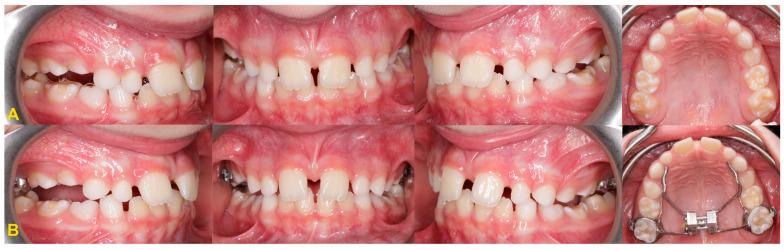

The gradual movement of a tooth away from the occlusal plane is called infraocclusion or reinclusion. Reincluded teeth are most often deciduous molars, and permanent teeth are less frequently affected. Depending on the level of the infraocclusion, the severity of the disorder is classified as mild, moderate, or severe. The etiology of the phenomenon is not fully known. Tooth submerging can lead to serious complications, such as abnormal position of adjacent teeth, displacement of the bud of the permanent successor, shortening of the dental arch, or developmental disturbances of alveolar process. Early diagnosis of the tooth infraocclusion and regular monitoring of its progression help to avoid serious permanent sequelae. The treatment of reinclusion often involves only observation. However, in some cases, the therapeutic procedure requires interdisciplinary treatment by specialists from various fields of dentistry. This study presents current methods of diagnosis and treatment of patients with submerged teeth.

牙齿逐渐离开咬合平面的运动称为低位咬合或再嵌入。再嵌入的牙齿多为乳牙,恒牙则较少受到影响。根据低位咬合的程度,疾病的严重程度分为轻度、中度和重度。该现象的病因尚未完全清楚。牙齿埋没可导致严重并发症,如邻牙位置异常、恒牙胚萌出受阻、牙弓缩短或牙槽骨发育障碍。早期诊断牙齿低位咬合并定期监测其进展有助于避免严重的永久性后遗症。再嵌入的治疗通常仅涉及观察。然而,在某些情况下,治疗过程需要由来自不同牙科领域的专家进行跨学科治疗。本研究介绍了目前诊断和治疗埋藏牙患者的方法。